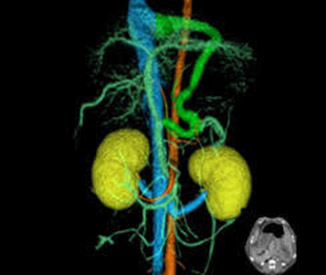

さらに精密検査のために血管造影CT検査を行ったところ、シャント血管が左胃静脈-横隔膜静脈を介した門脈-後大静脈シャントであることが判明しました。

左胃静脈-横隔膜静脈を介した門脈-後大静脈シャント。